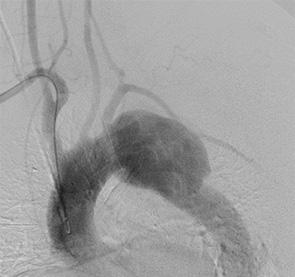

重症虚血肢に対するハイブリッド治療

腸骨動脈ステント(青矢印)・バイパス術(赤矢印)